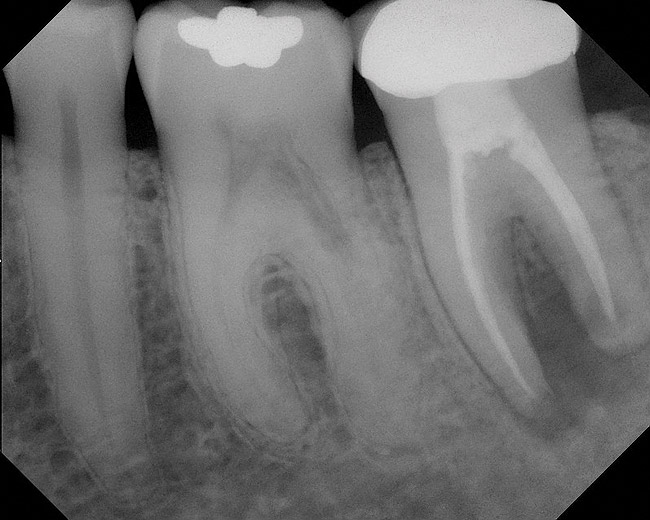

Figure 4  Clinical case of a lack of coronal seal that contributed to the failure of this root canal treatment.

Figure 4